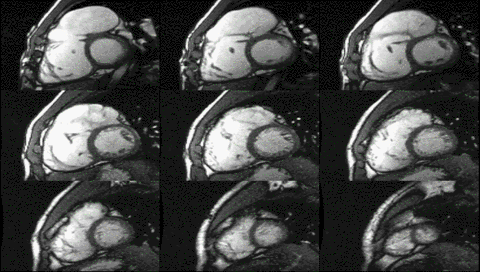

عملکرد قلب با استفاده از تصویربرداری ساین

اطلاعات عملکردی و ساختاری با استفاده از توالی ساین bSSFP بدست میآید. اینها معمولاً به صورت گذشته نگر و دارای کانتراست بسیار بالایی در تصویربرداری قلبی به دلیل نسبت نسبتاً زیاد T2: T1 خون در مقایسه با میوکارد هستند. تصاویر معمولاً برای دستیابی به طرحهای استاندارد قلبی که برای ارزیابی مورد استفاده قرار میگیرند، به صورت پی در پی برنامهریزی شدهاند. جریان پر تلاطم باعث برهم خوردن فاز میشود و از دست دادن سیگنال به بیماری دریچه ای اجازه قدردانی کیفی میدهد. ساینهای محور کوتاه بطن چپ از پایه به سمت حداکثر حفره بدست میآیند و برای کمی کردن حجمهای پایان دیاستولیک و سیستولیک انتهایی، و همچنین توده میوکارد استفاده میشود. توالی برچسب زدن الگوی شبکه که با انقباض قلبی تغییر شکل میدهد را تحریک میکند و باعث کرنش میشود.